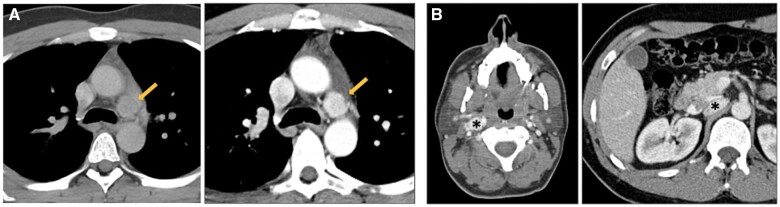

纵隔肿块是一组异质性的实体,具有多种组织病理学和放射学特征。影像学在纵隔异常的检测和解释中起着关键作用。CT仍然是首选的方式,因为它具有高空间和时间分辨率,并且能够评估组织组成,包括检测液体、脂肪和钙化。MRI在特定情况下是一种辅助工具,如区分复杂囊肿和实性病变或识别细胞内脂肪含量,如胸腺增生。纵隔肿块的鉴别诊断主要依赖于肿块的位置和组织组成,并结合患者的临床特征。这篇综述讨论了成人最常见的纵隔肿块,提供了一种主要基于优势密度模式和位置的实用方法来区分它们。

Mediastinal masses represent a heterogeneous group of entities characterized by a variety of histopathological and radiological features. Imaging plays a pivotal role in the detection and interpretation of mediastinal abnormalities. CT remains the modality of choice due to its high spatial and temporal resolution and its ability to assess tissue composition, including the detection of fluid, fat, and calcifications. MRI represents a complementary tool in specific scenarios, such as differentiating complicated cysts from solid lesions or identifying intracellular fat content, as seen in thymic hyperplasia. The differential diagnosis of mediastinal masses relies primarily on the location of the mass and tissue composition, integrated with clinical characteristics of the patient. This review discusses the most common mediastinal masses in adults, providing a practical approach to their differentiation mainly based on the predominant density pattern and location.